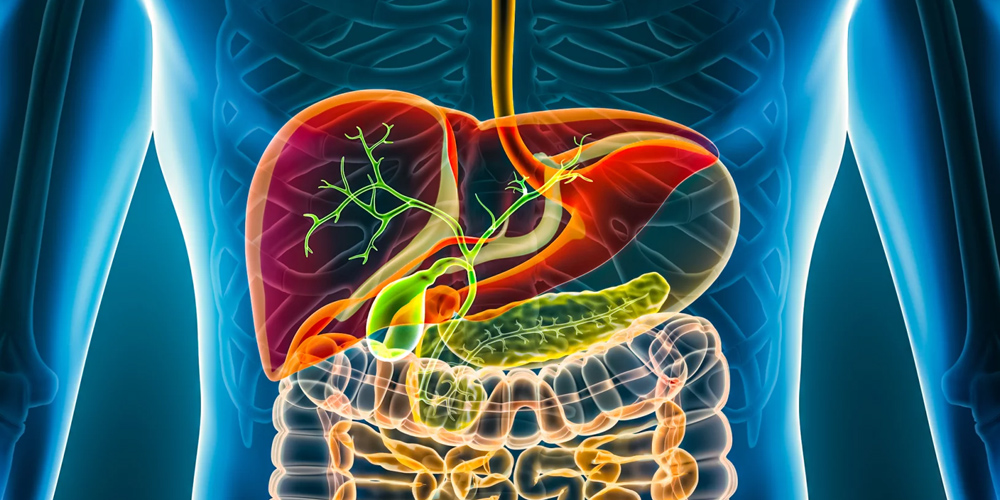

De mogelijkheden in de behandeling van patiënten met cholestatische leveraandoeningen nemen steeds verder toe en richtlijnen worden daarop aangepast. Dit webinar geeft inzicht in verschillende cholestatische leveraandoeningen: tijdig herkennen en - zo nodig - verwijzen, de mogelijke behandelopties en toekomstige ontwikkelingen.

In dit webinar bespreken experts de belangrijkste ziektebeelden binnen cholestatische leveraandoeningen: PBC, PSC en PFIC. Daarbij is veel ruimte voor praktische tips en casuïstiek om nieuwe behandelmogelijkheden een plek te geven in de dagelijkse praktijk.